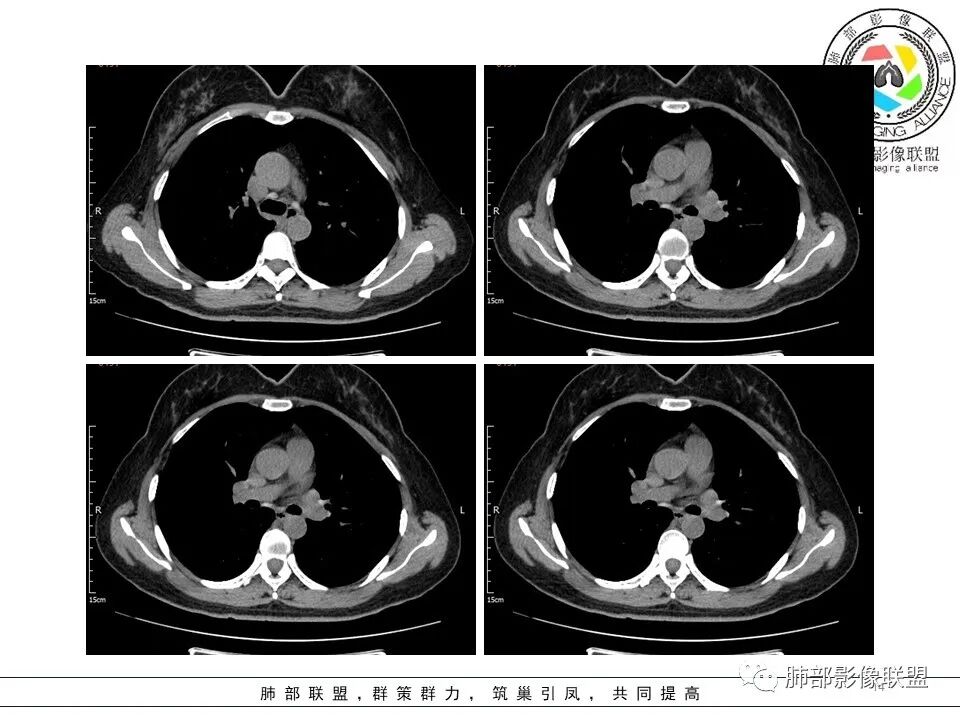

南边:左上肺病灶半年前就有。

是当时治疗后复查无变化?还是这次复查无变化?

这个差异大啊

分叶结节,内部结构杂乱,边缘板刷样毛刺,GGO边界清楚

胸膜牵拉

月牙铲?

常规要考虑腺癌

一般半年无变化,边缘GGO

GGO的形成主要由:炎性渗出、出血、肿瘤侵犯

出血,半年会变化,炎性渗出也会变化

当然还有就是纤维化病变可以表现GGO

但是纤维化病变,边缘收缩,条带状为主

按理慢性炎性病变,比较特异性的——结核要放待排,因为结核是妖